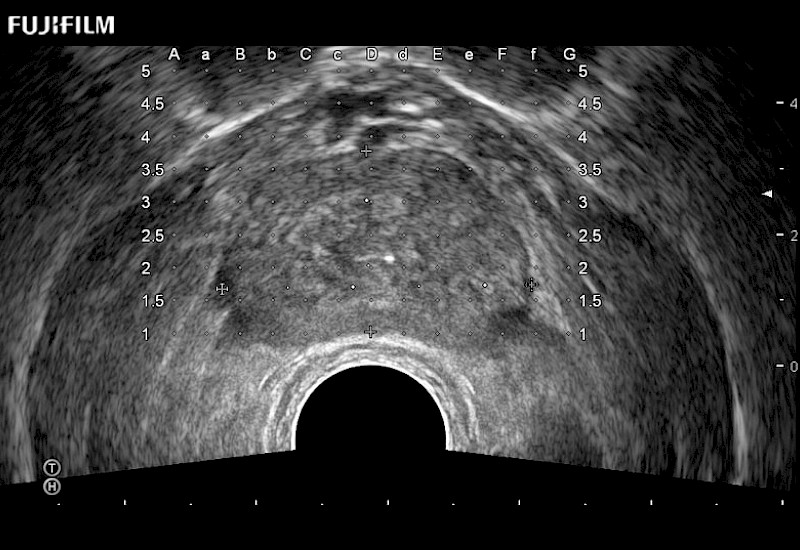

Exclusive 200° FOV end-fire prostate biopsy transducer.

Main Specifications: